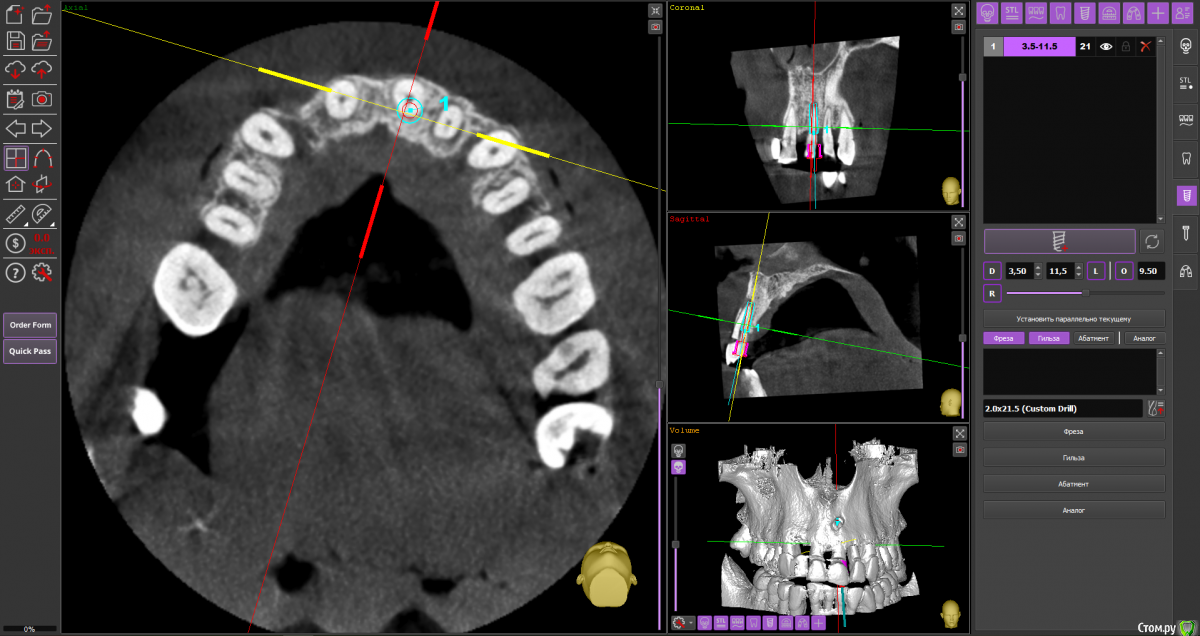

almaz7888 Опубликовано 28 января, 2021 Поделиться Опубликовано 28 января, 2021 Доброе утро коллеги! Планирую одномоментную имплантацию в область 2.1 зуба ( AnyRidge 3.5*11.5). В области апекса костный дефект. Думаю заполнить ксенографтом и перекрыть резорбируемой мембраной 1.5*2.0. Думал насчет спейсера Стоит ли такой имплант сразу нагрузить? или же лучше сделать адгезивный мост. Ссылка на комментарий

alboard Опубликовано 28 января, 2021 Поделиться Опубликовано 28 января, 2021 В том положении, которое на кт, сомневаюсь, что получите торк и сможете нагрузить... Взять подлиннее, поставить небнее и заглубить еще 4 Ссылка на комментарий

Irouil Опубликовано 28 января, 2021 Поделиться Опубликовано 28 января, 2021 Винт длиннее, выход в резцовый, стт, временная коронка 1 Ссылка на комментарий

almaz7888 Опубликовано 28 января, 2021 Автор Поделиться Опубликовано 28 января, 2021 Спасибо, тогда возьму 3.5*15. А резцовый нерв коагулирую и заполняю канал графтом или же можно без прижигания обойтись? Ссылка на комментарий

Astronaft Опубликовано 29 января, 2021 Поделиться Опубликовано 29 января, 2021 Я в похожей ситуации взял 4.5мм диаметр, БиоОсс и СТ трансплантат.AnyRidge тот который имеет сердцевину 3.5мм и глубокую агрессивную резьбу - очень хорошо врезается, риск лизиса кости меньше за счет места между витками. 2 Ссылка на комментарий